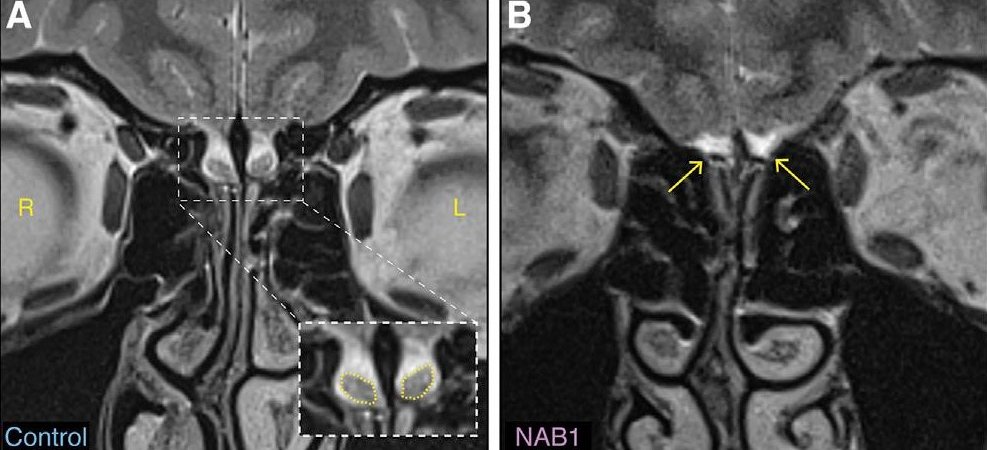

Istraživanje koje je objavljeno u časopisu Neuron pokazuje da neki ljudi imaju uobičajeno čulo mirisa, uprkos tome što im nedostaje deo mozga za koji se smatra da je presudan za miris – njušne sijalice.

Ipak, do velikog otkrića došlo je kada su istraživači sa Vajcmanovog instituta za nauku u Izraelu otkrili da postoje ljudi koji imaju uobičajen miris iako nemaju te sijalice.

Naučnici su naišli na prvi primer prilikom ispitivanja mozga ljudi sa zdravim čulom mirisa, kao deo potpuno nepovezane studije.

„Nismo mogli da nađemo sijalice u njenom mozgu, to je anomalija – ovo nema smisla, zar ne?“, kaže profesor Noam Sobel za BBC.

Žena je bila levoruka, a istraživači su želeli da uporede njen mozak sa snimcima drugih levorukih žena, kako bi videli šta se događa.

Morali su da skeniraju još devet mozgova pre nego što su pronašli drugu ženu bez sijalica, ali sa pucketavim čulom mirisa.

Pojava nikada nije otkrivena kod muškaraca, ali je prisutna kod više od četiri odsto levorukih žena.

Jedna od mogućnosti je da žene imaju mirisne sijalice, ali da su one toliko male da ne mogu da se vide na nekim skenerima.